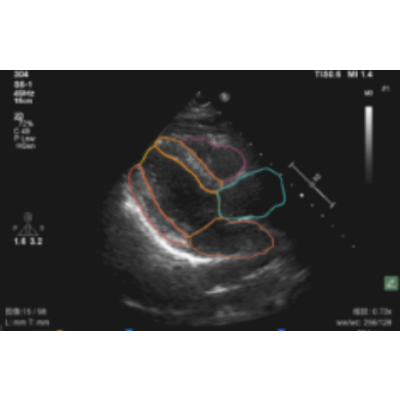

本软件利用AI技术可以自动识别超声心动图的标准切面,自动测量心脏和大血管的结构和功能参数,极大提高医生处置效率;自动测量多种心功能常规参数。

本软件采用独家动态影像处理技术+4D-flow+神经网络仿生机制+注意力机制,分别采用3万+心脏超声数据用于模型训练,重点模型算法有切面质量评估、切面分类模型、切面重点区域分割、心动周期识别切面、频谱波形轮廓和关键点识别模型和算法组成。